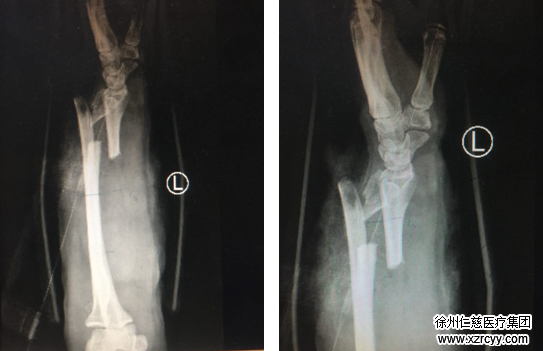

“患者来到我们医院后,生命体征不稳定,左前臂接近毁损状,基本上被判了‘死刑’。但看着患者家人不愿放弃的眼神,我们医护人员的意志也更加坚定了,保肢,无论如何都要保肢!”唐洪伟医生说,患者肢体污染非常严重,伤口贯通,肌肉毁损,伤口内有大量辣椒粉末等残留。术中给予反复冲洗,清创,血管移植,将血管、神经、肌肉、肌腱进行修复,并用外固定支架固定住粉碎性骨折的桡骨,用克氏针和钢丝将骨折的尺骨进行内固定,手术一切顺利。目前患者的再植肢体已经成活,正处于康复阶段。